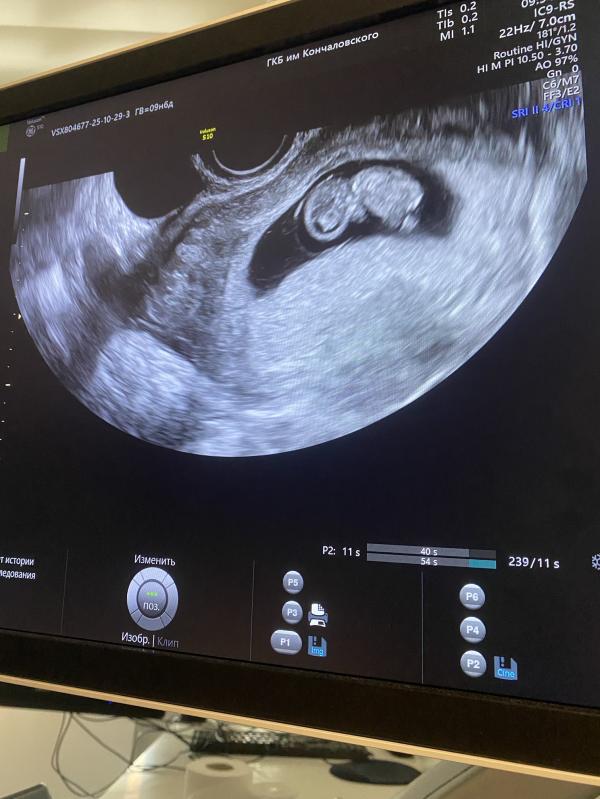

Сходила на нормальное узи , все хорошо и ножки и почки уже все видно даже мозг 😍